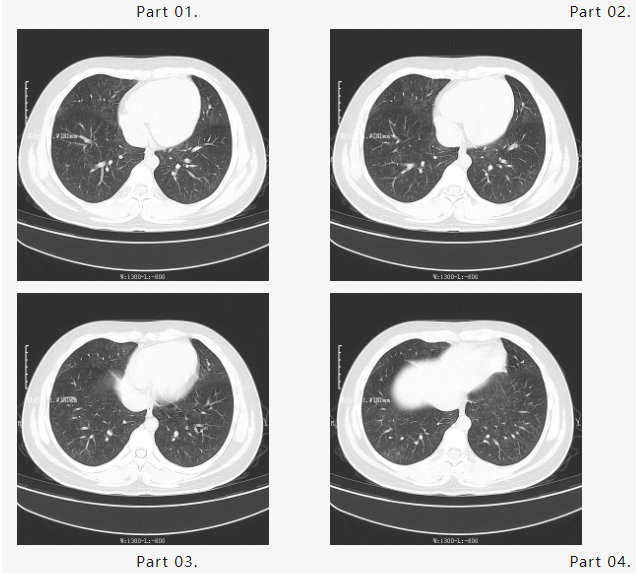

刚入院时胸部CT结果显示如下:

检查结果回示,小毛肺部病灶弥漫,双肺见多发片状磨毛玻璃影,呈现“白肺”表现,小毛感染非常重,新型冠状病毒核酸阳性,呼吸道多种病原体靶向测序报告结果显示:鲍曼不动杆菌感染,感染较重立即下病危通知。